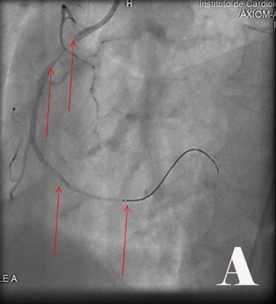

Fig. Abordaje invasivo emergente en paciente con Angina inestable de Alto riesgo y cambios electrocardiográficos atípicos con FEVI muy baja.

Fig. Se visualizó obstrucciones largas proximal y distal de 90 % de coronaria derecha (CD) (2A). Se realizó ACTPs y coloco 2 Stens convencionales (2B). Obstrucción de tercio proximal de 90 % de arteria coronaria de descendente anterior (DA) y del 95 % de la circunfleja izquierda (CX) (2C), se le realizó ACTP y colocó Stens a la DA fármacoactivo pero por el riego-beneficio se decidió no hacer nada en CX (2D).